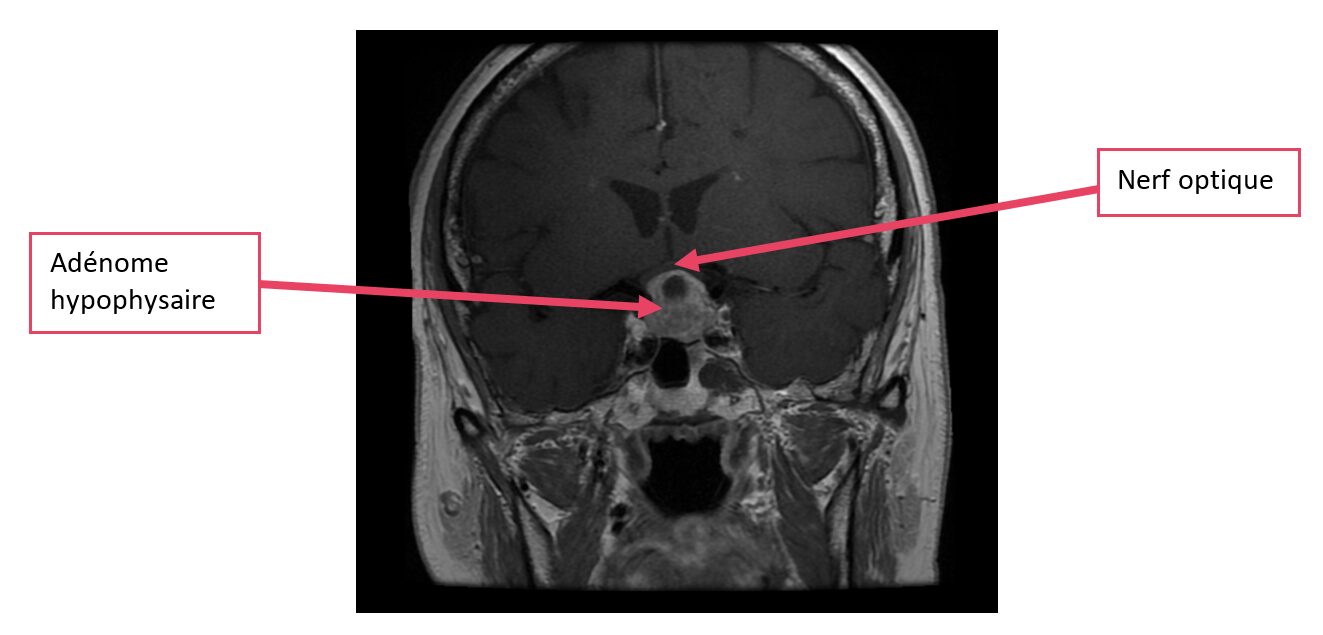

L’adénome peut être découvert en cas de production excessive de certaines hormones (troubles des menstruations, écoulement mammaire, modification du visage, des mains des pieds, diabète, syndrome d’apnée du sommeil, hypertension artérielle…) ou par compression des structures nerveuses à proximité comme le nerf optique (vision floue, maux de tête…), mais il peut être asymptomatique et découvert sur une imagerie cérébrale réalisée pour des symptômes sans rapport avec l’adénome (découverte fortuite).

adénome hypophysaire

Macroadénome hypophysaire (flèche rose) pré et post opératoire